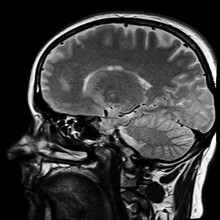

По результатам нового исследования, опубликованного 6 августа в «Journal of the American Society of Nephrology», заболевания почек могут вызывать нарушения мозговой деятельности.

В исследовании были изучены клинические данные 2600 пациентов из Нидерландов. Анализ информации показал, что нарушения работы почек тесно связаны с нарушением кровоснабжения головного мозга. Исследователи также обнаружили повышенный риск инсультов и деменции у пациентов с заболеваниями почек. Связь оказалась независимой от известных факторов риска, связанных с заболеваниями сердца.

Исследователи отметили, что риск нарушения мозговой деятельности может наблюдаться не только у пациентов с хронической болезнью почек, но и у пациентов, страдающих менее серьезными заболеваниями почек.